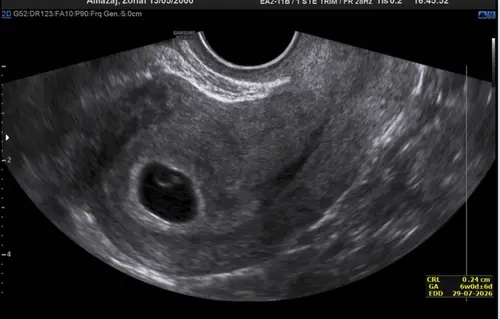

Gisteren gehad was 5+6weken, heb er nog een staan 11 december den ben ik normaal 7 weken

Het is trouwens de eerste keer dat ik iets in het vruchtzakje zie normaal was die altijd leeg en kwam op een miskraam